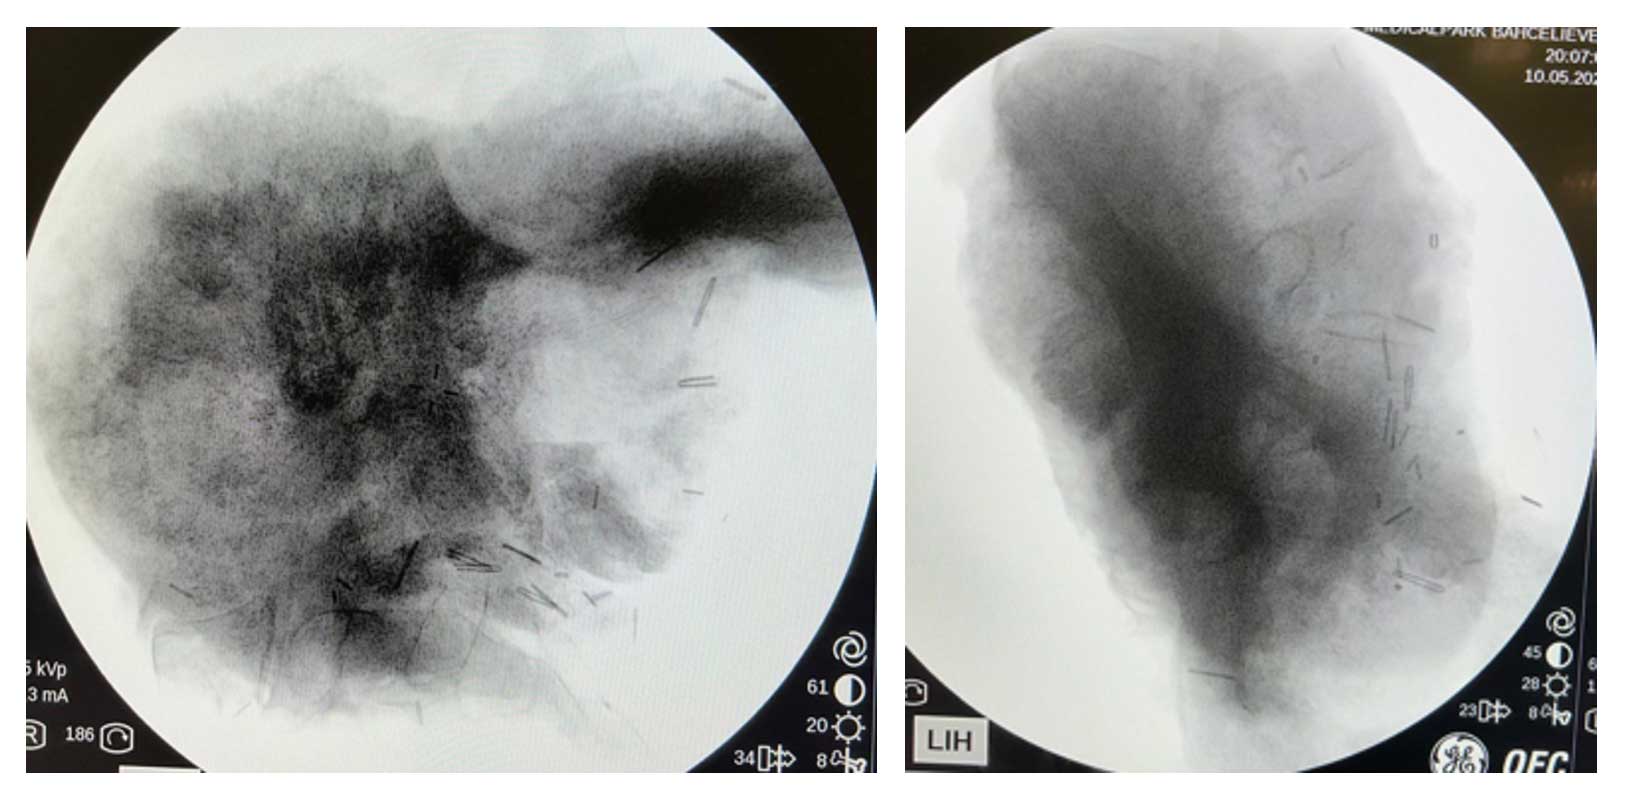

Ameliyat Esnası: Çıkarılan tümör dokusunun skopi görüntüsü.

Ameliyat Sonrası: Röntgende rezeksiyon sonrası görülmekte.